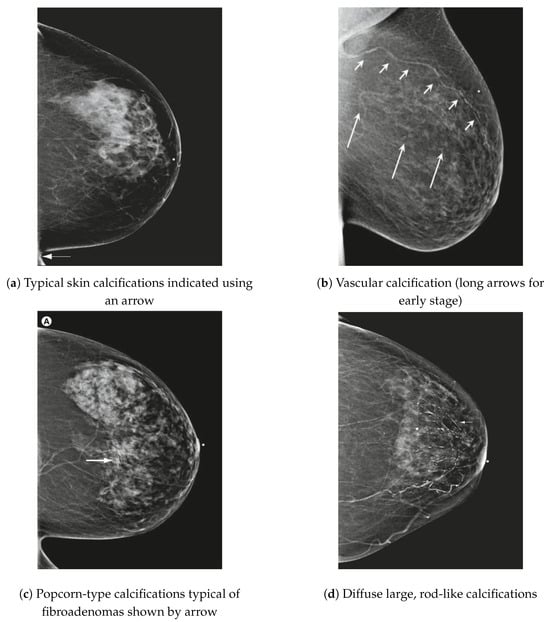

Kandlikar and Satish G et al. in [13] indicate that microcalcifications (MCs) are essential indicators for detecting breast cancer in mammograms. Clustered MCs characterize malignant breast cancer with a linear branching pattern involving more than three MCs, each less than 0.5 mm in diameter. In contrast, benign conditions typically present as individual MCs. Figure 6 illustrates various common microcalcifications (MCs) identified in mammographic images, highlighting their diverse morphological characteristics.

Figure 6.

Several common types of MCs observed in mammograms [14].